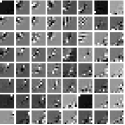

IV-A Transform Learning

To better understand the potential of the MRST model, we vary the number of layers and pre-learn transforms for ST, MRST2, MRST3, MRST5, and MRST7, which possess , , , , and layers, respectively. We used 7 slices of the Mayo Clinic data to train the models. For each model, we run 1000 to 2000 iterations of the learning algorithm to ensure convergence. Fig. 1 shows some of the learned transforms, with each transform matrix row displayed as a square patch for simplicity. The single layer transform displays edge-like and directional structures that sparsify the image. However, with more layers, finer level features are learned to sparsify transform domain residuals in deeper layers. Nonetheless, transforms in deep layers could be more easily contaminated with noise in the training data, since the main image features are successively filtered out over layers.